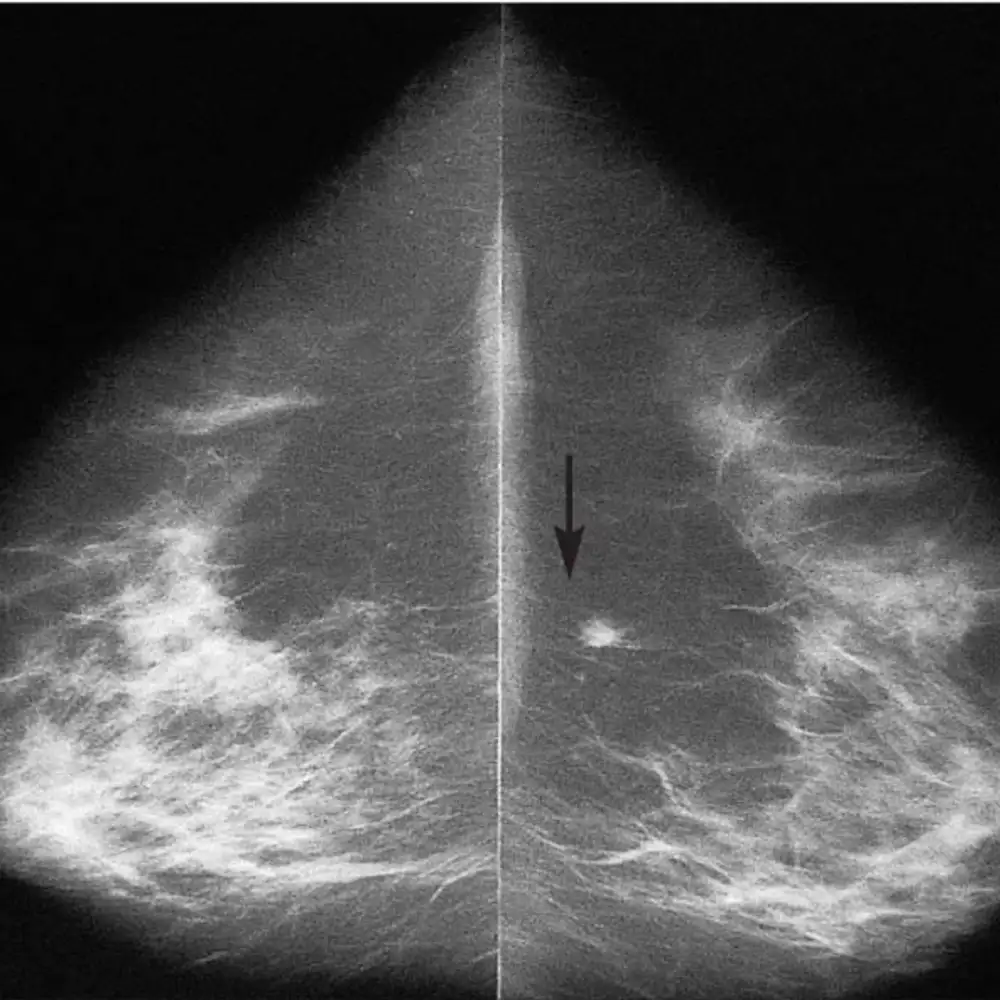

Screening